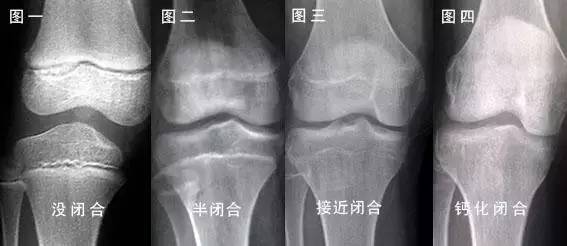

性早熟患儿的性激素会提前大量分泌,此时生长速率比同年龄、同性别儿童明显加快,身高明显增加,骨龄也比实际年龄提前。

骨骺提前闭合后,成骨细胞的分泌器官不存在了,骨骼就不可能再生长了,孩子就无法再长高,直接造成成年矮小。